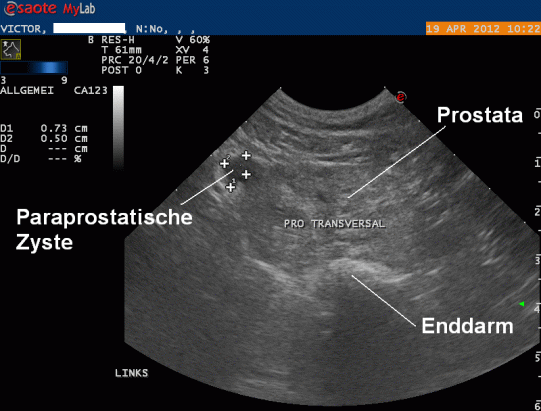

Die Prostata erscheint sonografisch verändert: Sie ist vergrössert, enthält Regionen von unterschiedlicher Echodichte sowie viele kleine und kleinste Cysten. Auf der linken Seite findet sich ausserdem ein aussen der Prostata anliegende, kleine sogenannte paraprostatische Zyste. Die Prostataveränderungen sind vereinbar mit einer gutartigen, altersbedingten sogenannten Prostatahyperplasie - wie beim Mann kann sich die Prostata auch beim Rüden im Laufe des Lebens unter ständigem Testosteroneinfluss vergrössern und strukturell verändern.

Um herauszufinden, ob es sich bei der paraprostatischen Zyste möglicherweise um einen Abszess oder Folge eines Tumors handelt, wird die Zyste punktiert und entleert. Zytologisch werden keine Bakterien gefunden; allerdings kann ein Prostatatumor nicht komplett ausgeschlossen werden.